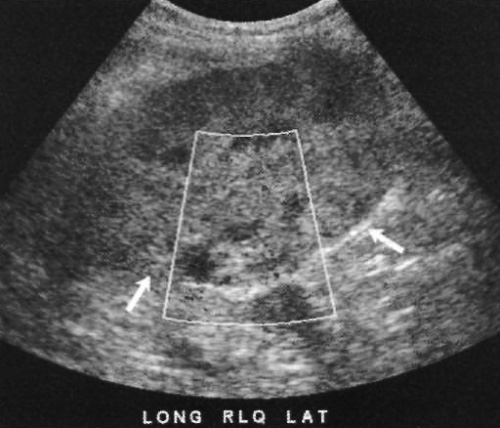

Со временем при лизировании гематома становится гипо- или анэхогенной по отношению к почечной паренхиме, часто наблюдаются внутренние перегородки (фото 10). На этом этапе проще установить диагноз. При этом может возникнуть впечатление, что гематома увеличивается, хотя на самом деле она просто лучше визуализируется. В большинстве случаев гематомы разрешаются самостоятельно в течение нескольких месяцев без необходимости проведения дренирования, кроме случаев инфицирования или если гематома оказывает серьезное давление на почку, нарушая ее функцию.

Фото 10. Гематома. А – продольное ультразвуковое изображение: курсорами обозначен эхогенный участок скопления жидкости, который локализован выше и кпереди от трансплантата почки (Т) и смещает его назад. В – поперечное ультразвуковое изображение того же пациента, выполненное через 10 дней после первого исследования: стрелками обозначен гипоэхогенный участок (скопление жидкости) в нижнем левом квадранте